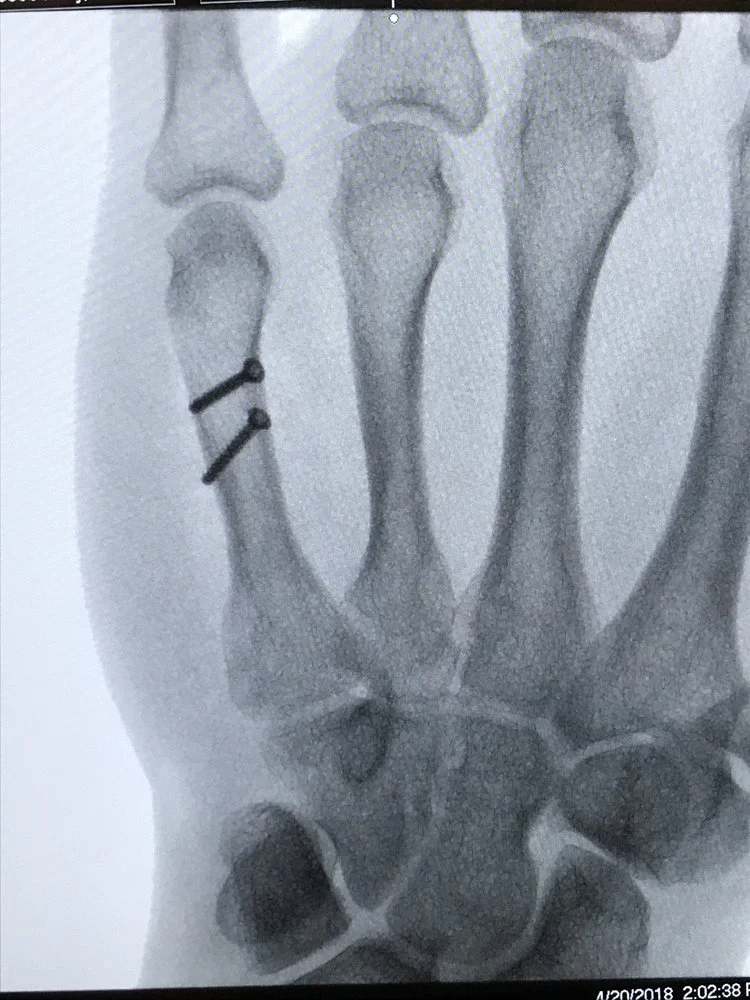

Metacarpal Fracture